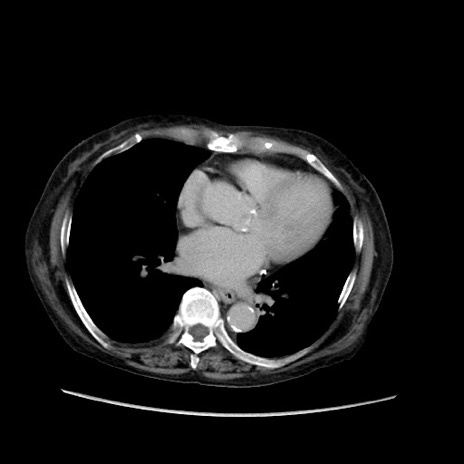

症例31(横断像)

【症例】80歳代 女性

【主訴】腹部膨満感

【現病歴】他院にて肝硬変にてフォロー中。1週間前から便秘、腹部膨満感、臍部腫瘤あり受診となる。

【既往歴】肝硬変

【身体所見】腹部膨隆あり、皮膚変化なし、疼痛なし。

【データ】WBC 4600、CRP 0.25